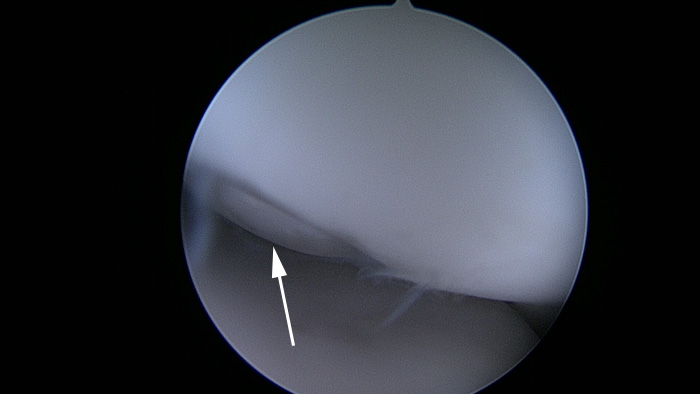

La flèche indique l’emplacement d’un fragment qui s’est libéré.

La zone malade a cicatrisé, produisant une revêtement cicatriciel qui ressemble à du cartilage.